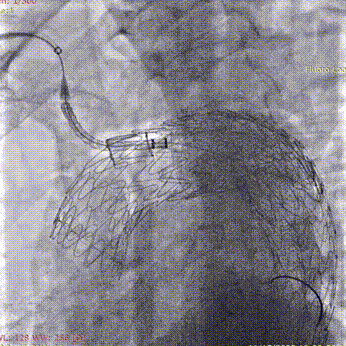

7. 沿斑马导丝送入TBE分支支架(型号:TSB121506W),释放分支支架。

斑马导丝是治疗什么的「胸有乾坤」至简至易 行之有效—— Zone 0 TBE植入治疗弓部动脉瘤病例报道_https://www.jmylbn.com_新闻资讯_第21张

导入分支支架

斑马导丝是治疗什么的「胸有乾坤」至简至易 行之有效—— Zone 0 TBE植入治疗弓部动脉瘤病例报道_https://www.jmylbn.com_新闻资讯_第22张

释放分支支架

8. 球囊扩充分支支架。